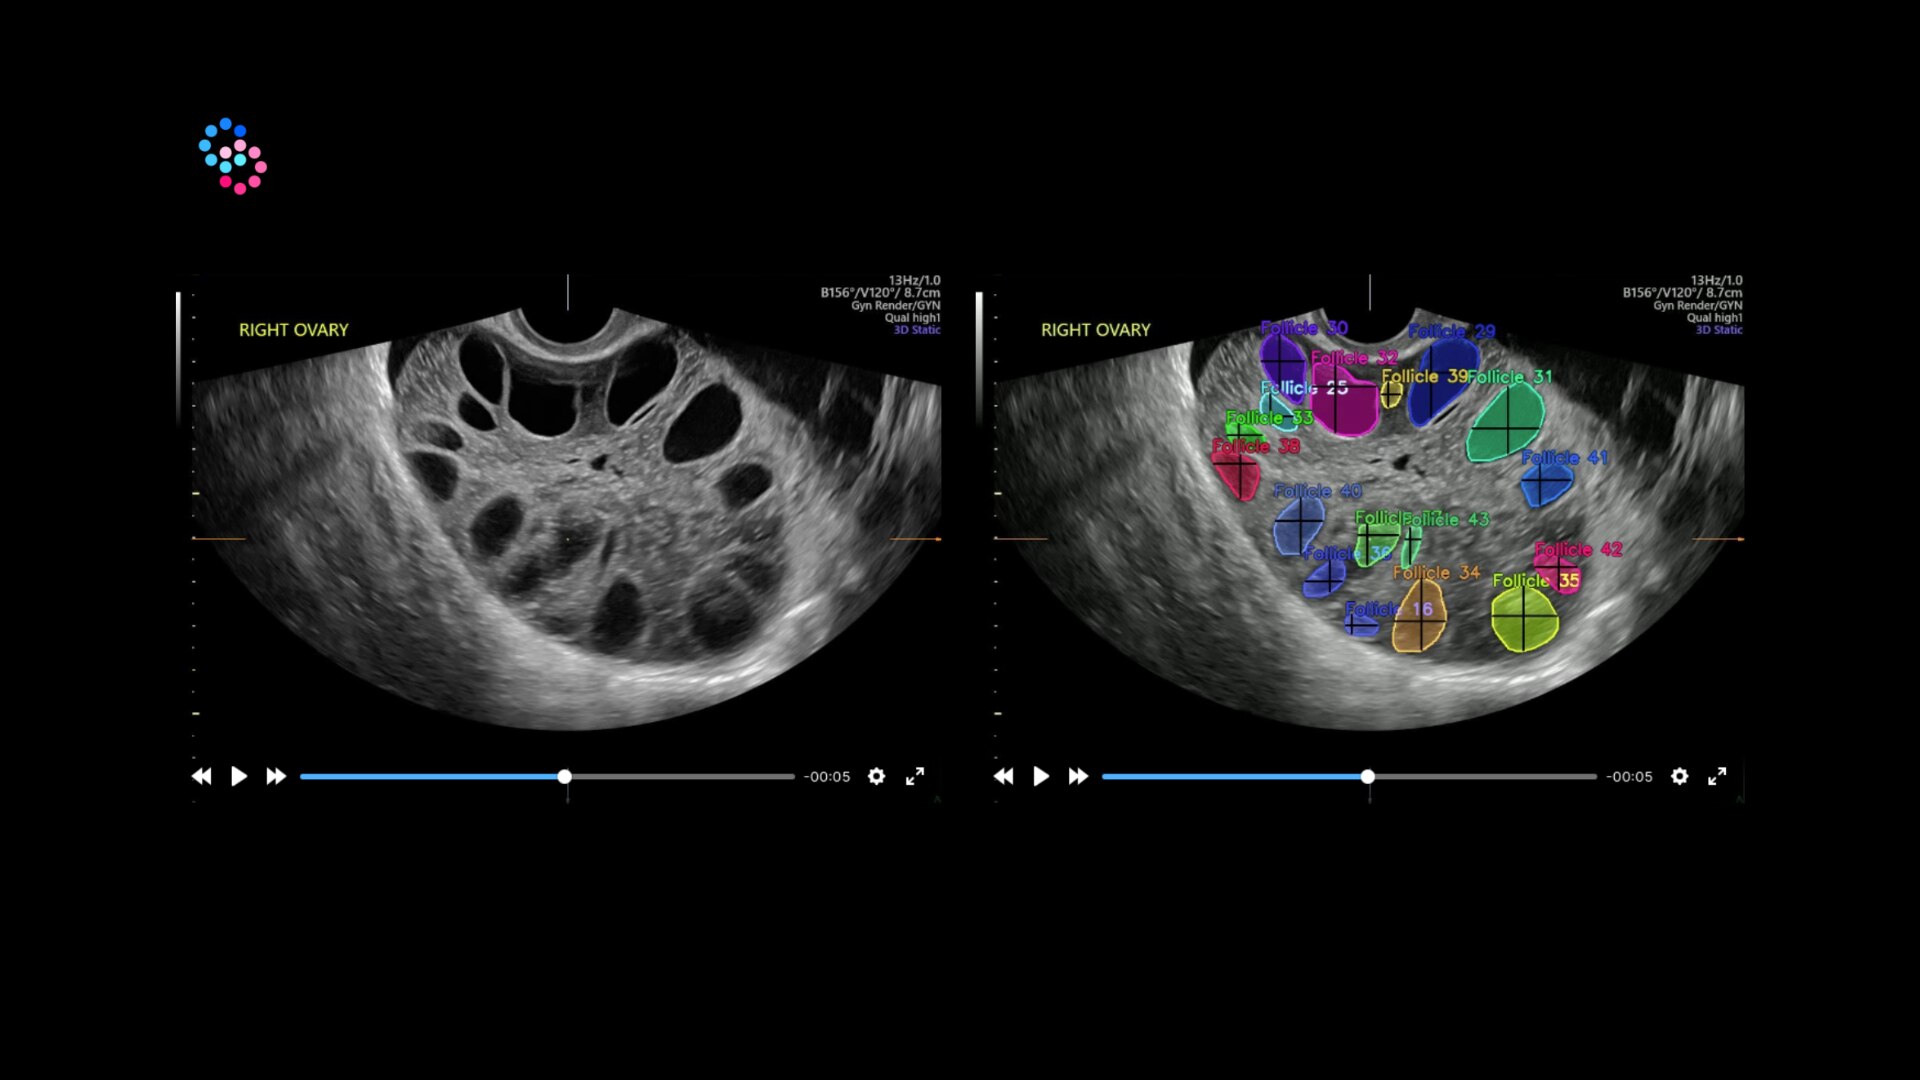

Scalability: Robust, standard features and scalable options to configure the optimal system to meet your abdominal, cardiac, OB/GYN, vascular, breast, and musculoskeletal imaging needs.